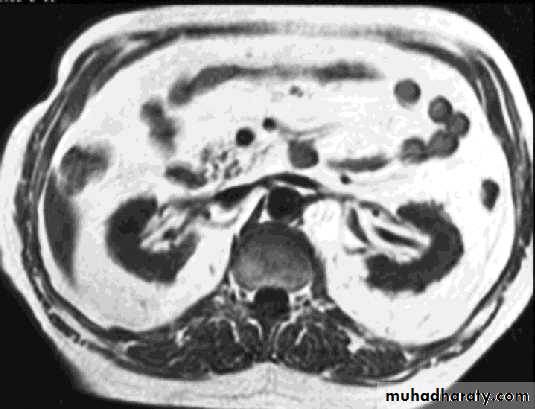

ComparisonsMRI image

CAT image

abdomen

Compare bone and soft tissue density